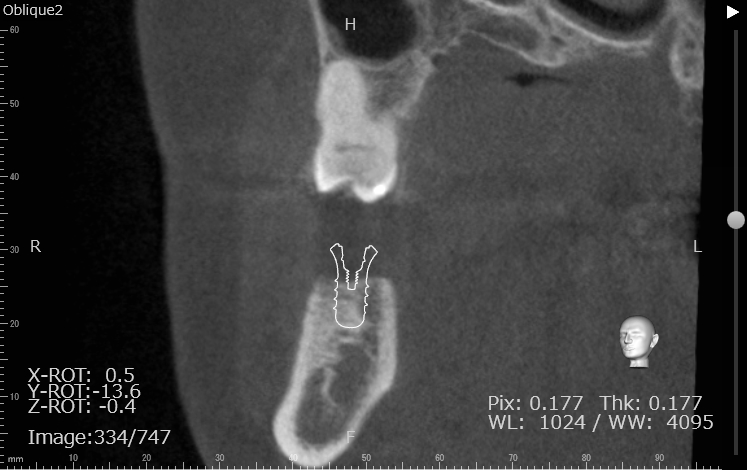

Case7

術前

術中

術後

| 治療名 | 抜歯即時インプラントとソケットリフトによる上顎臼歯部の修復症例 |

|---|---|

| 治療説明 |

歯の根が破折していたため抜歯が必要となり、患者さんとご相談のうえ、インプラントによる治療を選択しました。 ただし、インプラントを支える骨の高さが不足していたため、**上顎洞に骨を足す“ソケットリフト”**を併用し、安全にインプラントを埋入しました。 |

| 治療回数・期間 | 約3ヶ月 |

| 副作用とリスク |

・入れ歯や従来のブリッジと比べて、治療期間が長くなる傾向があります。 |

| 料金(税込) | 小規模GBR:110,000円 ソケットリフト:165,000円 インプラント一次手術:220,000円 二次手術:55,000円 上部構造〈セラミック〉:165,000円 合計:715,000円 |